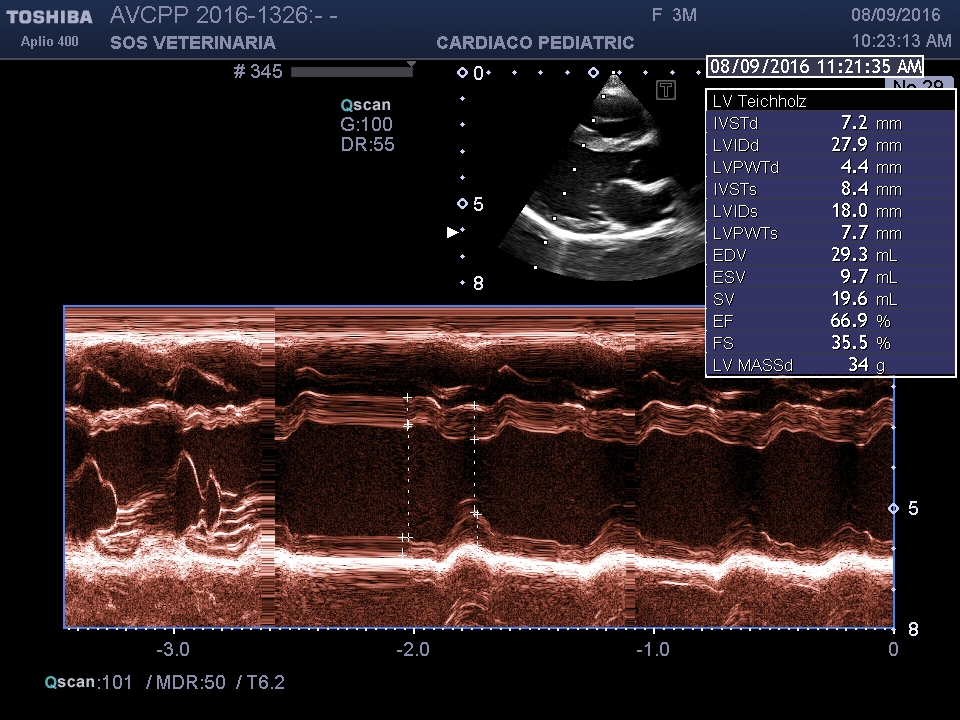

Valori di riferimento per un soggetto di 5 kg di peso LVIDd 19-22 e LVDs 11-13 , in questo soggetto abbiamo rispettivamente 26-27 e 18-21 valori che denunciano un significativo sovraccarico volumetrico e scompenso sistolico .

Comunemente un DIV di piccole dimensioni con un gradiente superiore a 100 mmHg (normalmente la pressioni sistolica nel Vsx e’ di 120 mmHg mentre in quello di destra e’ di soli 20-25

mmHg il gradiente tra le due camere deve essere quindi almeno di 100 mmHg) non e’ in grado di sovraccaricare il ventricolo sx e tanto meno di indurre una insufficienza miocardica , diversamente quando il gradiente tende a scendere indica un sovraccarico pressorio significativo e la probabile evoluzione verso lo scompenso cardiaco (overcirculation sovraccarico in polmonare-atrio sx -ventricolo sx fino ad arrivare allo scompenso).